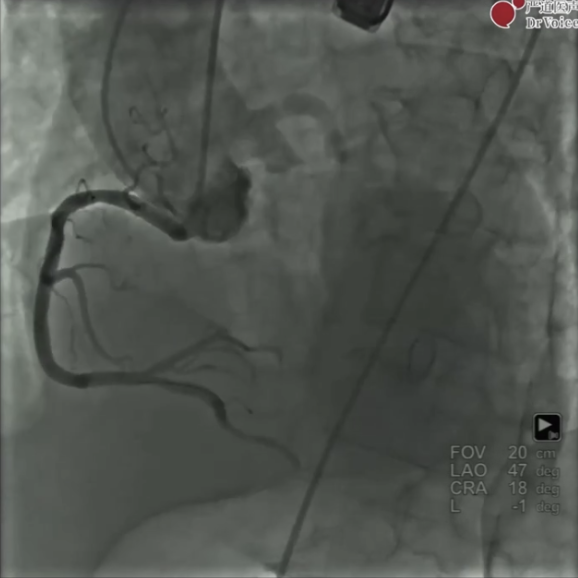

术前超声示:主动脉瓣重度狭窄合并中度关闭不全,CTA示:大瓣环,重度钙化,RCA开口异常,冠脉存在风险。

图片术前主动脉根部造影

图片术后瓣膜释放后造影

综合患者术前评估结果,洪浪教授表示该病例病情复杂,瓣膜选择downsize可能更为安全,同时自身瓣膜或可提供一定的锚定支撑力,保障手术安全进行。

术中使用小球囊进行不完全预扩张,随后洪浪教授独立扭动输送系统手柄,在snare保护下瓣膜输送不顺利,随后重新对输送系统进行调整,最终单人完成瓣膜过弓、定位,快速起搏状态下释放瓣膜,患者血流动力学参数满意。

整个手术过程中,洪浪教授与讨论嘉宾实时交流,就瓣膜downsize、烟囱支架保护冠脉、球囊后扩张等重要临床问题发表见解,每一步操作都经过深思熟虑。而术中使用的VitaFlow Liberty™电动可回收系统能够让术者流畅地进行独立操作,同时可以有效进行冠脉保护,最终两例手术都获得了理想效果。